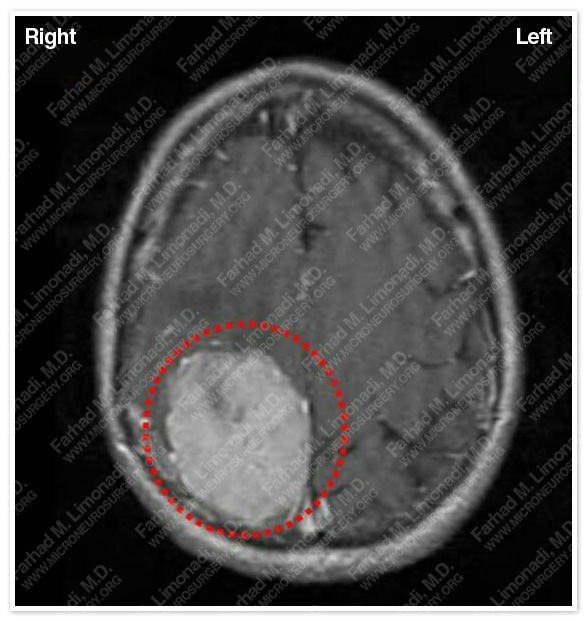

Imaging

MRI scan of his brain showed a large right parieto-occipital tumor radiographically consistent with meningioma. Tumor is outlined in a red dotted circle.